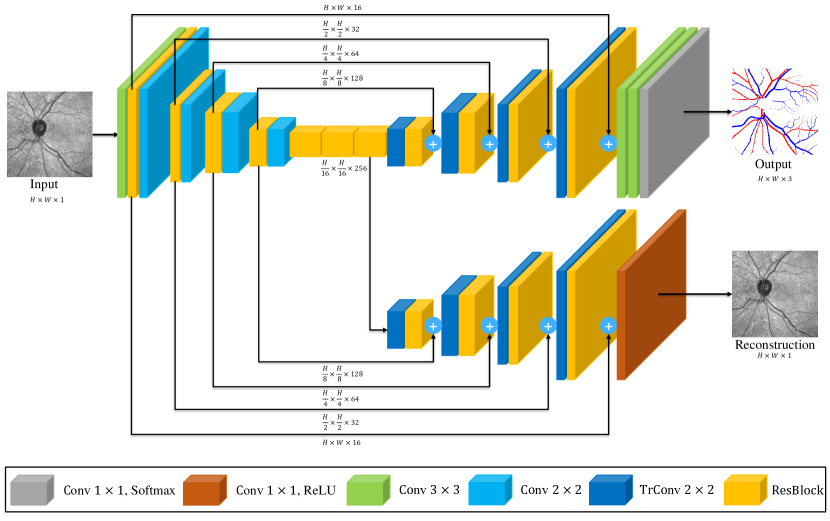

Additionally, we propose a novel knowledge distillation framework for the domain adaptation from IR to color images of models pretrained on the RAVIR dataset. We demonstrate the effectiveness of our domain adaptation approach by fine-tuning and testing SegRAVIR on three popular color retinal vessel segmentation datasets, DRIVE, STARE, and CHASE_DB1.

IV-D Knowledge Adaptation via Distillation

Knowledge distillation [50][51], which was originally proposed as a model compression methodology, enables the training of a smaller student model under the supervision of a larger pretrained teacher network. We leverage knowledge distillation as a feature alignment mechanism for the domain adaptation of RAVIR-pretrained networks to color retinal images. Specifically, we first use transfer learning to create a teacher network in the new modality (color) from a pretrained SegRAVIR model. For this purpose, we use the main stream (encoder and segmentation decoder) of a SegRAVIR network and initialize the weights from a previous pretrained checkpoint. However, we replace the last layer of the network with a convolutional layer whose weights are randomly initialized, followed by a softmax activation layer to account for the single output channel of the target segmentation task (i.e., binary vessel segmentation). We fine-tune this teacher network on the target image modality.

Furthermore, we create a student network with the same architecture and supervise its segmentation outputs according to the soft labels generated by the teacher network predictions. Fig. 3 overviews the proposed strategy.

Specifically, let denote the pixel-wise output logits of the teacher network. We employ temperature scaling to generate soft labels with smoother probability distributions, hence enabling the identification of inter-class relationships, according to

| (6) |

Similarly, we generate soft labels by applying temperature scaling to the output logits of the student network. Consequently, the distillation loss is calculated as

| (7) |

where is a hyper-parameter, denotes the segmentation ground truth, and denotes the KL divergence loss.

As is shown in Section VII, our adaptation via distillation strategy is more effective than naive transfer learning, since it addresses the domain gap between the RAVIR dataset and color fundus image datasets by feature alignment in the target space through KL divergence minimization.

VI-C Knowledge Distillation

In Table IX, we present the segmentation performance of SegRAVIR, with different pretraining strategies, on the DRIVE, STARE [9], and CHASE_DB1 datasets. To validate the effectiveness of our proposed knowledge distillation approach, we compared against the RAVIR network pretrained on the RAVIR dataset as well as the network with random weight initialization. On the DRIVE and STARE datasets, our approach yields and improvements in Dice score, respectively, relative to random weight initialization and and relative to pretrained weight initialization. Similarly, on the CHASE_DB1 dataset, our approach outperforms random and pretrained weight initialization by 6.71% and 2.86% in terms of the Dice score, respectively.